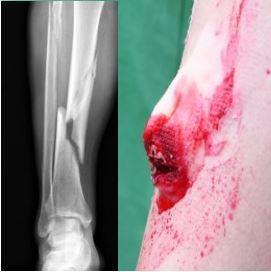

Skill 210A – Botbreuken en/of wervelletsel

Bij gesloten botbreuk

Bij open botbreuk